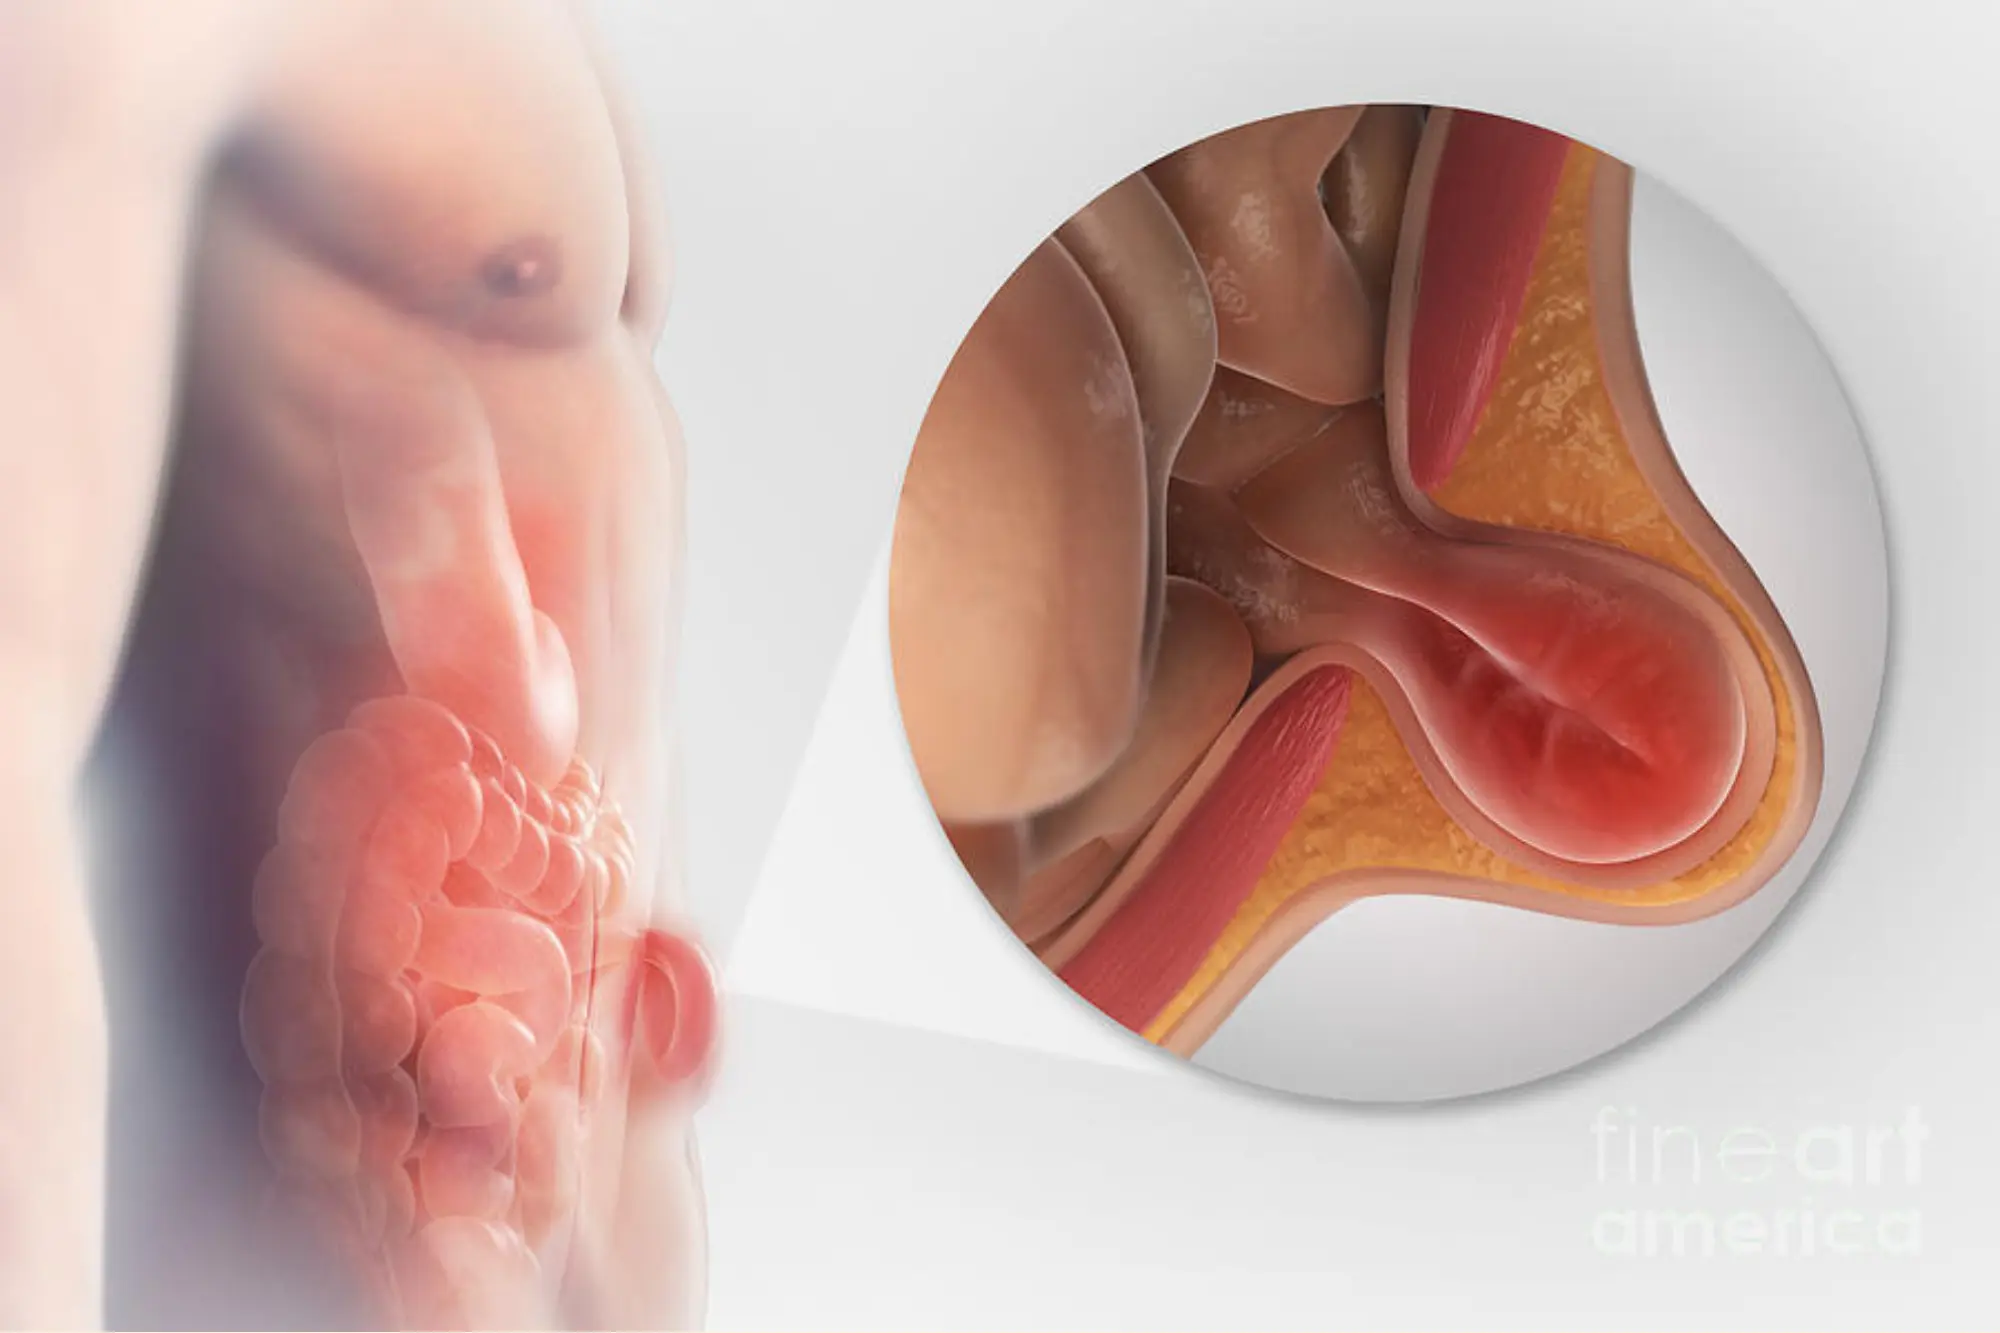

Bilateral Inguinal Hernia

A laparoscopic solution for a common yet uncomfortable issue, Inguinal Hernia surgery helps you return to your routine with minimal downtime and scars.

An inguinal hernia occurs when a portion of tissue, such as the intestine, pushes through a weak spot in the abdominal muscles near the groin. It may result in a visible bulge and discomfort, especially while lifting, bending, or coughing. Laparoscopic inguinal hernia repair is a minimally invasive method to correct this condition with fewer complications and a quicker recovery than open surgery.

- Laparoscopic hernia repair (TAPP or TEP technique)

- Mesh placement to reinforce the wall